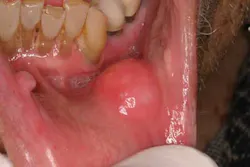

The lips: The lips should be evaluated with the mouth open and closed, noting any abnormalities in symmetry, contour, color, or texture. Attention to the vermilion border of the lower lip is warranted as this is a prime site for oral cancers. First, revert the lower lip and inspect the inner surface. The labial mucosa should be smooth and uniform in color. Notice the frenum of the lip in the midline. Note any signs of smokeless tobacco use (ulcers, red or white discolorations, texture variations) on the labial mucosa. With the lip still retracted, one can also inspect the gingivolabial sulcus, the gingival mucosa, and the teeth. Next, palpate the lip with your thumb and index finger, noting any firm or nodular submucosal areas (figure 1). Repeat these steps for the upper lip.

Figure 1